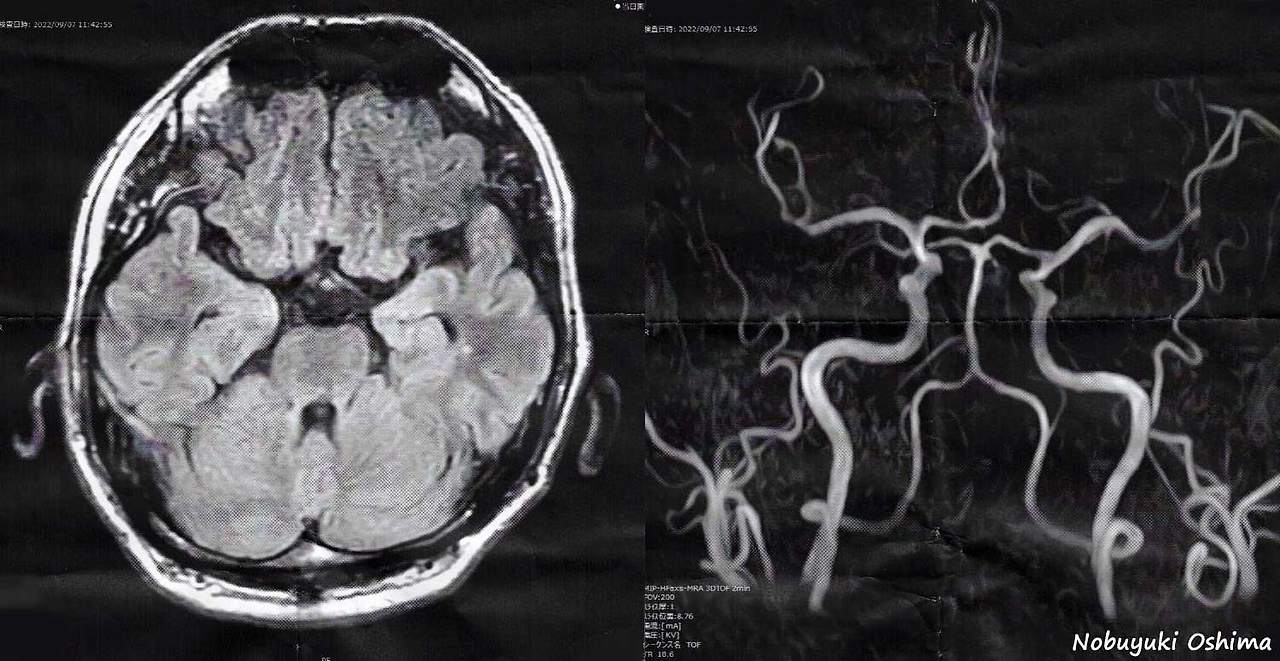

뇌 MRI 검사는 뇌혈관질환, 뇌종양, 뇌출혈, 신경학적 이상 증상 등을 평가할 때 필수적으로 활용되는 정밀 진단 장비이며, 강한 자기장을 이용해 인체 내부를 고해상도로 촬영하는 방식입니다. 최근 두통, 어지럼, 이상감각, 시야 흐림 등 다양한 증상에서 MRI 검사가 권고되는 사례가 증가하면서 많은 분들이 검사 비용, 촬영 시간, 조영제 여부에 따른 금식 필요성 등을 궁금해합니다.

뇌 MRI 비용은 급여(보험 적용)인지 비급여(전액 자부담)인지에 따라 크게 구분됩니다. 증상 여부, 의사의 의학적 판단이 결정적인 기준이 되며 조영제 유무 또한 비용에 직접적으로 영향을 미칩니다.

- 조영제 사용 목적

- 종양이나 염증 등 특정 병변을 더 명확하게 보기 위해 시행